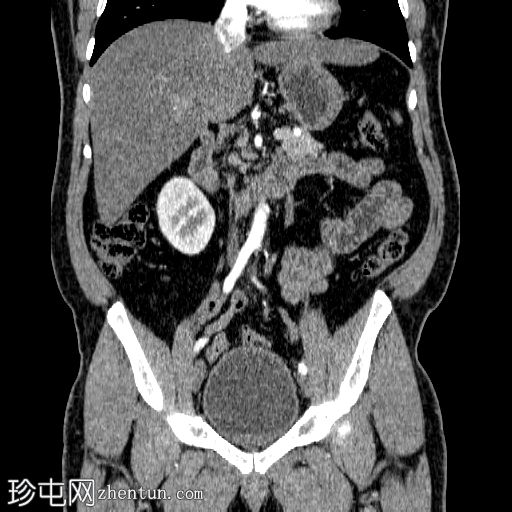

冠状位增强扫描

门静脉期

在左侧输尿管膀胱连接处可见一枚24×15 mm的大膀胱结石。膀胱壁轻度弥漫性增厚,厚度约6 mm,提示膀胱炎。

左肾上极发现一单纯性皮质囊肿,Bosniak I 型,大小为 13 mm。

可见多个副脾(脾小体),位于主脾实质的上方和下方,在影像学各期均表现出与脾脏相似的衰减值。

肝脏弥漫性脂肪浸润。